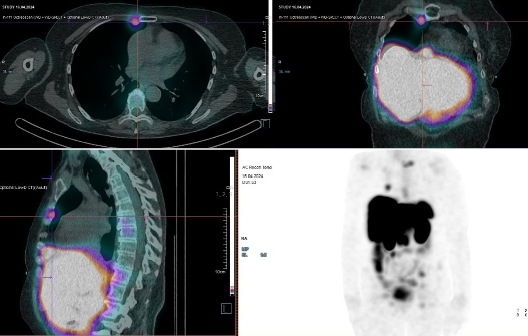

/ Obr. č. 3: Fúze SPECT/CT 4 hod. po aplikaci OctreoScanu. /

/ Obr. č. 4: Fúze SPECT/CT 4 hod. po aplikaci OctreoScanu. /

/ Obr. č. 5: Fúze SPECT/CT 4 hod. po aplikaci OctreoScanu. /

/ Obr. č. 7: Fúze SPECT/CT 4 hod. po aplikaci OctreoScanu. /

/ Obr. č. 8: Fúze SPECT/CT 24 hod. po aplikaci OctreoScanu. /

Popis: pozorujeme patologická ložiska zvýšené depozice radiofarmaka-nově nekontrastně ve více LU v levém nadklíčku, v jedné parasternální LU vpravo (úroveň Th6) vel. 10 mm, v LU v dolním mediastinu prekardiálně cca 17 mm, tomograficky zachycena chabě zvýšená akumulace RF v Th páteři v úrovni obratlového těla Th7 a Th8 (v ldCT bez patologického korelátu, nově však v ldCT obraze zjištěna v. s. lýza pravého postranního výběžku obratle Th8), v levém jaterním laloku - S4b, v pravém jaterním laloku - S5 a S6, v LU paraaortálně v úrovni L2/3 15,5 mm - dnes okrsek nápadnější, chabě v levé kosti kyčelní dorsálně při SIS - částečná regrese od min. vyšetření.

Nález svědčí pro přítomnost vícečetných patologických ložisek zvýšené denzity somatostatinových receptorů ve výše uvedených lokalizacích. Ve srovnání s posledním vyšetřením jsou detekována nová ložiska v levém nadklíčku a mediastinu, susp. diskrétní nález i v Th páteři (obratel Th7 a Th8) se zachycenou lýzou postranního výběžku obratle Th8 vpravo v CT obraze, částečná regrese okrsku v levé kosti kyčelní oproti minulému vyšetření.